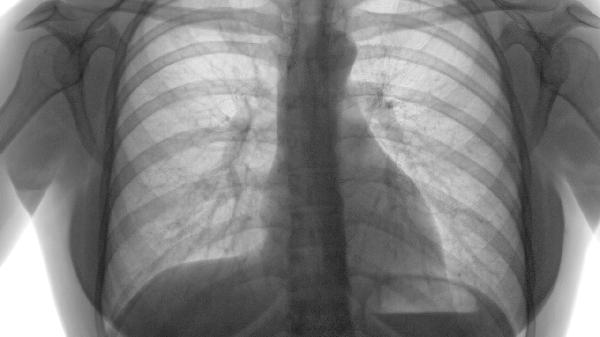

肺积液指液体异常积聚在肺组织或胸膜腔,主要与肺部感染、心力衰竭、恶性肿瘤三类原因有关。

肺癌或转移癌侵犯胸膜时,肿瘤细胞阻塞淋巴管或分泌异常物质,导致胸膜腔积液。此类积液多为血性,需通过病理检查确诊。治疗包括胸腔闭式引流、胸腔灌注化疗药物或靶向治疗控制原发肿瘤。

肺积液患者应保持半卧位减轻呼吸困难,限制每日钠盐摄入低于3克,避免剧烈活动。可适当食用冬瓜、薏仁等利水食物,监测体重变化及血氧饱和度。若出现呼吸急促、口唇发绀等症状需立即就医,长期反复积液者需定期复查胸部影像学评估病情进展。